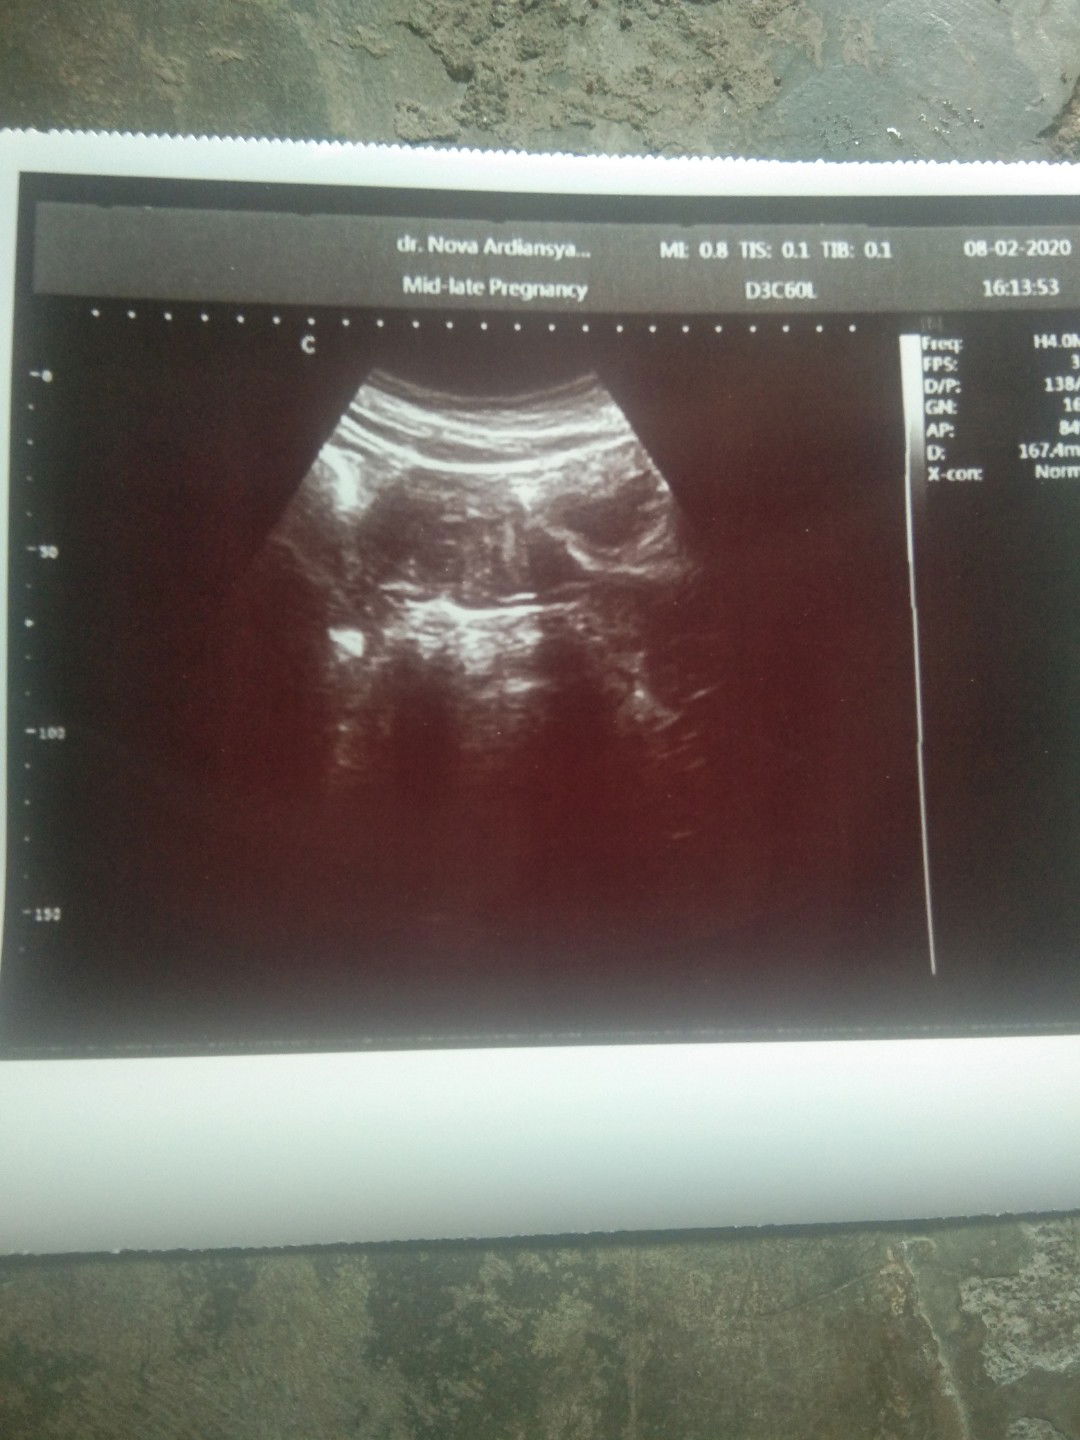

Baby twins SYAHILLA&SYAQEENA

Alhamdulillah sudah lahir my baby twins,di uk 35minggu JK perempuan, BBL 2,4kg,dengan proses normal. Buat bunda** yg sdang menanti HPL smoga diperlancar persalinan nya.